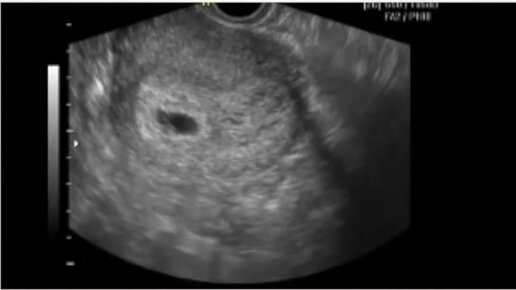

УЗИ на 6 неделе беременности